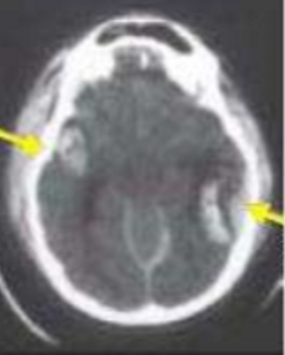

quesqui est illustré par les fleches ?

A

COntusion cérébrale

le fameux COUP et CONTRCOUP